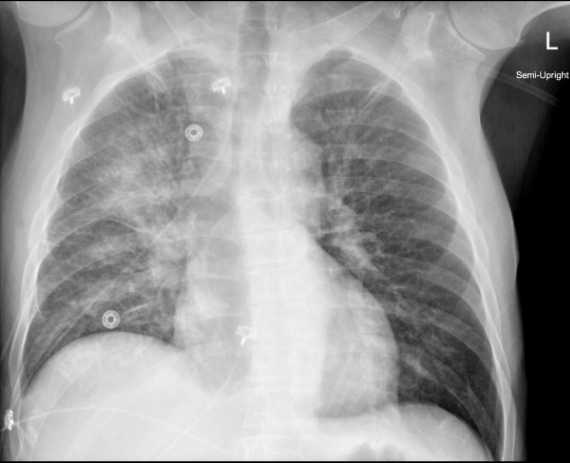

Acute MR에서 심전도는 보통 정상이며 원인이 되는 질환(심근경색, 좌심실비대)이 있다면 이를 나타냅니다. P-mitrale가 있다면 chronic MR이 있었을 것으로 추정해 볼 수 있습니다. 흉부 엑스레이도 보통 정상 크기의 심장을 나타내면서 폐부종 소견을 보입니다. Interstitial and alveolar edema는 보통 양측성이지만 때때로(한 연구에서 9 %) 폐부종은 일측성이기도 하고 전형적으로는 RUL에 국한됩니다. 다음 예로 든 흉부 엑스레이는 unilateral pulmonary edema from acute MR 케이스의 사진입니다. Acute MR 환자들은 폐부종과 쇼크로 내원하기 때문에 내과적, 외과적 응급입니다. 대부분의 경우 확실한 치료는 즉각적인 수술입니다. 그러나 진단이 이루어지는 시간과 수술을 대기하는 동안 약물 치료가 필요하기도 합니다.